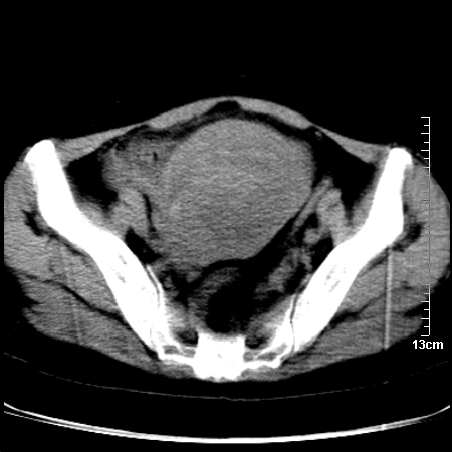

术前的疏忽,手术前诊断阑尾炎,但是没有常规做b超,导致术后1周检查发现 1。实性包块?2。腹腔术后脓肿?

病史:病人一周前诊断阑尾炎,未做b超,手术发现阑尾化脓,(没有留意有无包块),术后1周病人发热,血象:1.6万,做b超发现,随ct检查,上传图片

巨大囊实性包块,边界大部尚清楚,不太像脓肿的表现。应该做个增强检查除外盆腔肿瘤。

盆腔一边界大部份清晰囊实性肿块,其周腹脂未见确切异常,其一端与右侧附件相连。考虑右侧附件肿瘤。

因术前未做相关检查,故漏诊完全有可能!若脓肿这么大,临床不会单纯是阑尾炎的体征!支持:盆腔肿瘤——首选:附件来源的肿瘤,建议增强扫描!!!

我在为一名女高中生做阑尾炎术前b超常规检查时发现右侧附件区囊性占位,其中可见脂类回声,遂诊断畸胎瘤,后经妇科及外科联合手术证实,该病例不是与我的那例巧合吧.